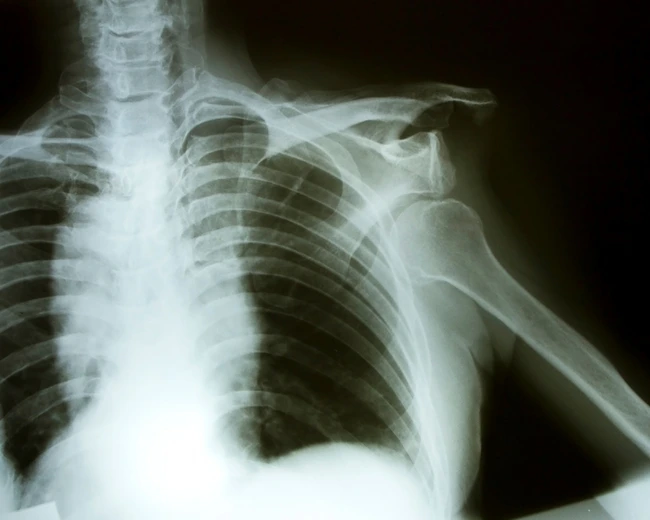

Lauren a fost supusă la cinci intervenţii medicale, fără a avea însă vreun rezultat      FOTO Shutter

Tusea, strănutul şi chiar cea mai mică smucitură, cum ar fi simpla trecere peste obstacolele pentru reducerea vitezei, înseamnă un coşmar pentru o britanică în vârstă de 20 de ani. Lauren Harry spune că un efort atât de banal duce la dislocarea umărului său chiar şi de zece ori pe zi.

Medicii cred că suferă de sindromul Ehlers-Danlos (SED), o afecţiune genetică ce se manifestă prin modificări ale colagenului, materialul care asigură structura şi rezistenţa tegumentului şi a ţesutului osos. Colagenul ei este atât de slab, încât nu-i poate susţine membrele.

Lauren acuză dureri de picioare de când avea 11 ani, dar i s-a spus că sunt durerile fireşti ale creşterii. La 15 ani a căzut cu cârjele în timp ce participa la un festival, rănindu-şi umărul. De atunci, umerii şi încheieturile, inclusiv genunchii şi degetele, i se dislocă frecvent, potrivit „Daily Mail“.

Ea a fost supusă la cinci intervenţii medicale pentru stabilizarea umerilor, dar problema nu a putut fi rezolvată. „Am suferit câteva intervenţii care mi-au fixat oasele pentru o perioadă, dar nu a durat mai mult de nouă luni până la o nouă dislocare. Umerii mei se dislocă de 10 ori pe zi, fie că strănut, tuşesc sau trec peste un obstacol cu limitare de viteză“, a declarat Lauren.